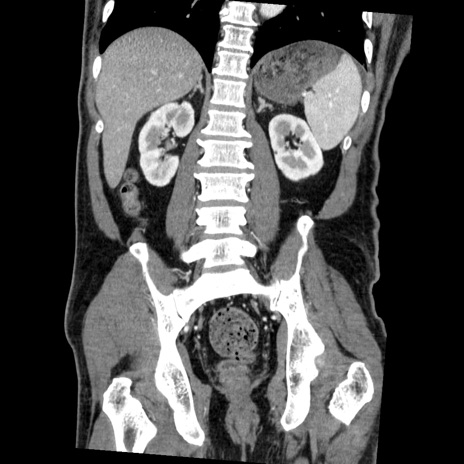

症例22(冠状断像)

【症例】50歳代男性

【主訴】腹痛

【現病歴】AVMからの被殻出血のため回復期リハ病棟入院中。 本日午後3時頃急に下腹部痛が出現した。

【既往歴】AVM、被殻出血、虫垂炎、高血圧

【身体所見】意識晴明、左半身不全麻痺、会話の理解は良好、36.5°C、腹部:膨隆、全体に板状硬、下腹部正中に圧痛点あり、反跳痛-、筋性防御不明、右下腹部にope scar

【データ】WBC 9400、CRP 0.06